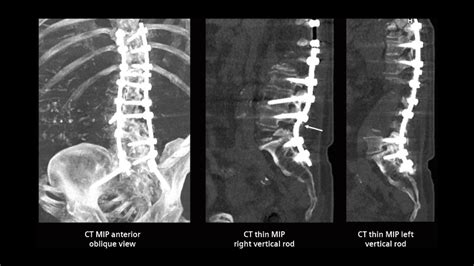

Advancements in medical technology have made the fusion of lumbar surgery more precise and less invasive than in decades past. During the operation, the surgeon clears the damaged disc material or bony overgrowths that are compressing the nerves. Once the site is prepared, the surgeon inserts a bone graft—which may be harvested from the patient's hip, obtained from a bone bank, or manufactured as a synthetic bone morphogenetic protein.

To ensure the bones fuse correctly, the surgeon usually employs internal fixation devices, such as titanium screws, rods, or plates. These components act as a bridge, holding the vertebrae in place while the graft integrates into the living bone. The table below outlines the primary types of approaches used by surgeons today.